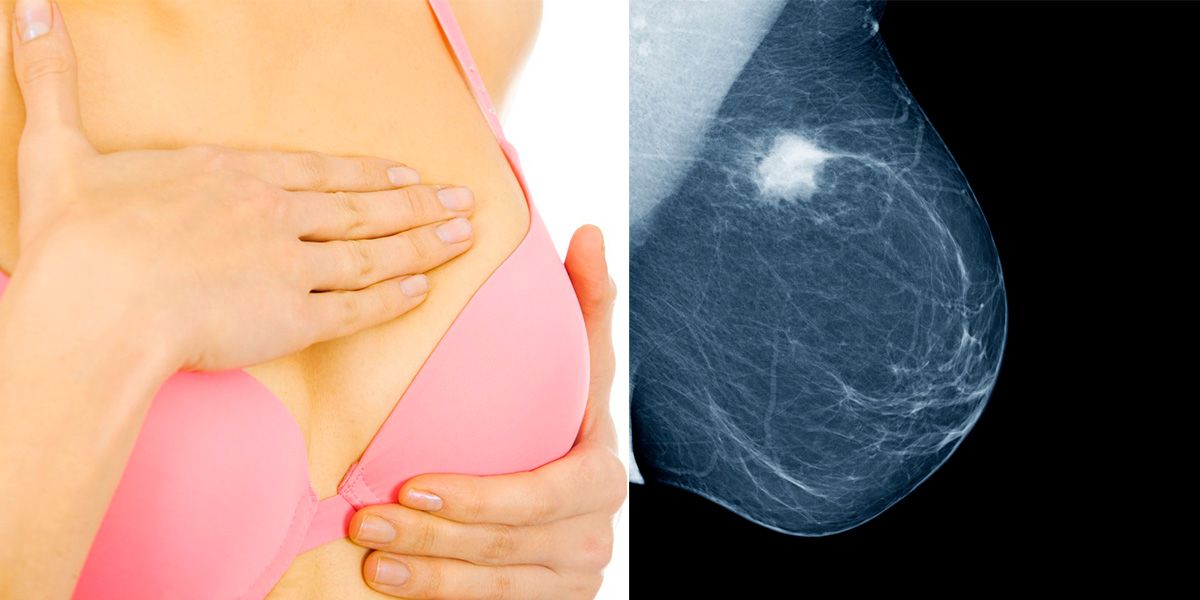

Brustkrebs ist die häufigste Krebserkrankung der Frau mit 5.000 bis 5.500 neuen Fällen pro Jahr in Österreich.